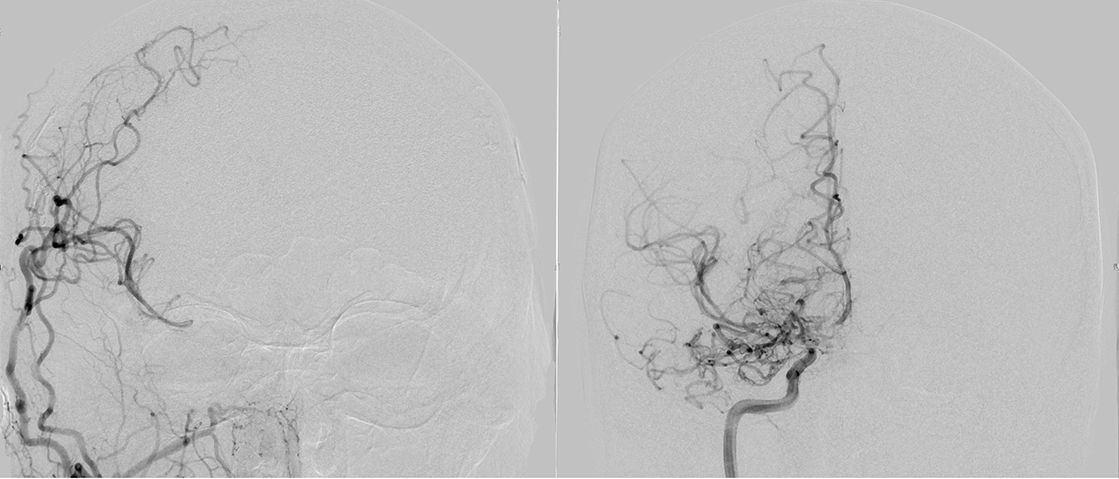

Bypasschirurgie bei anderweitigem/atherosklerotischem Hirnarterienverschluss

atherosklerotischem Hirnarterienverschluss

Hirnarterienverschlüsse der großen zuführenden Gefäße können verschiedene Ursachen haben. Sofern nicht die Moyamoya Krankheit ursächlich ist, sondern beispielsweise Atherosklerose (Carotisstenose, Carotisverschluss, Mediastenose, Mediaverschluss), muss ebenfalls sorgfältig überprüft werden, ob ein extrakranieller-intrakranieller Bypass (EC-IC Bypass) indiziert ist, oder nicht. Bei stattgehabten schweren Infarkten (maligner Mediainfarkt) kann nicht revaskularisiert werden, da das Hirngewebe großflächig infarziert ist. Sofern jedoch nur kleine Infarkte oder gar nur TIAs (transiente ischämische Attacken) aufgetreten sind, muss die Option eines Bypasses ebenfalls kritisch geprüft werden. Dies gilt insbesondere für Patienten, die trotz konservativer Therapie (Minimierung der Risikofaktoren, Einnahme von Blutverdünnern) weiterhin wiederholt Symptome verspüren.

Eine operative Therapie ist dann nach vergleichbaren Maßstäben zu indizieren, wie bei der Moyamoya Krankheit, der operative Ablauf vergleichbar. Auf Grund unserer großen Expertise im Bereich der Bypasschirurgie kann eine operative Therapie, sofern notwendig, mit großer Sicherheit angeboten werden.